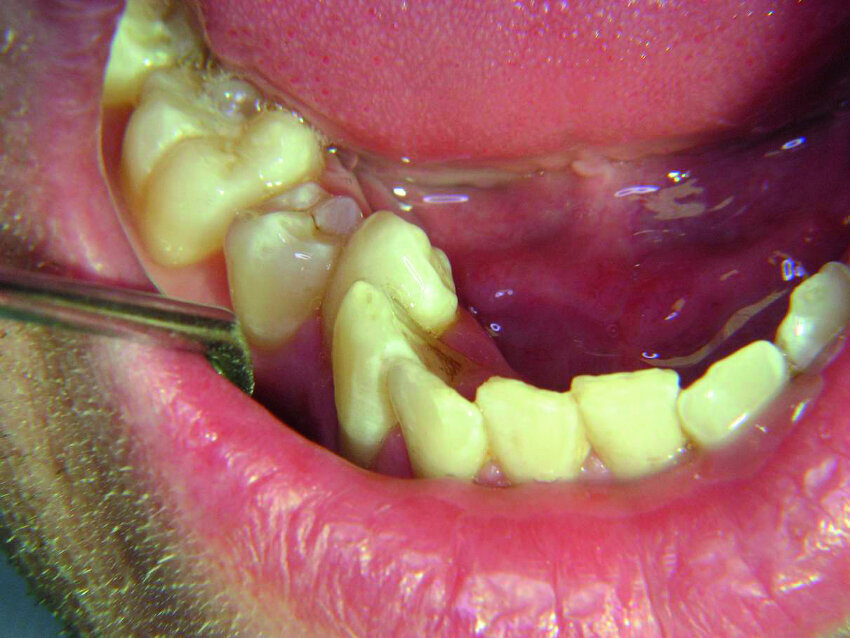

Les deuxièmes prémolaires peuvent être résumées par les mots « je veux créer » ou « mon moi créatif » (Fig. 3). La deuxième prémolaire supérieure droite symbolise ce que l’on veut développer dans le monde extérieur, nos enfants ou nos hobbies, et la deuxième prémolaire supérieure gauche nos dons naturels. La deuxième prémolaire inférieure droite, similairement à la première prémolaire adjacente, témoigne de notre capacité d’accomplir nos projets, particulièrement dans le domaine du travail. Ainsi, après la restauration d’une anodontie au moyen d’un bridge sur inlay, une jeune patiente dans l’indécision a terminé brillamment ses études au grand bonheur de ses parents (Fig. 4). Par contre les figures 5 et 6 sont des photographies de patients chez qui l’évolution professionnelle se place toujours au second rang des priorités.